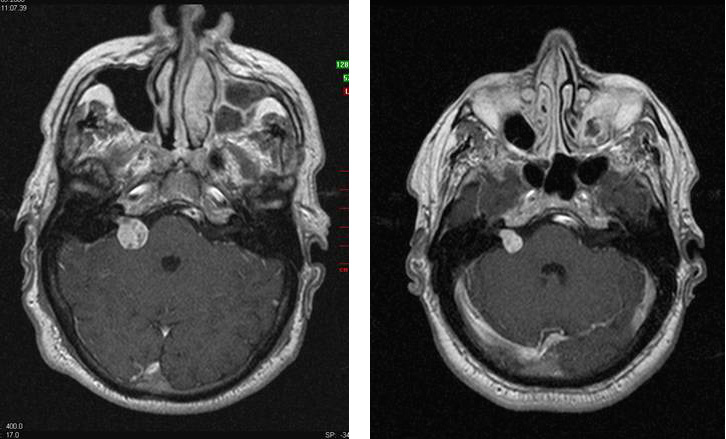

Im MRT-Bild links ist ein Akustikusneurinom erkennbar, welches sich in den rechten Kleinhirn-Brückenwinkel ausdehnt. Das Kontroll-Bild rechts erfolgte 2,5 Jahre nach der einmaligen Cyberknife Behandlung. Es zeigt sich eine typische Narbe im inneren Gehörgang. Der gutartige Tumor ist ausgeschaltet.